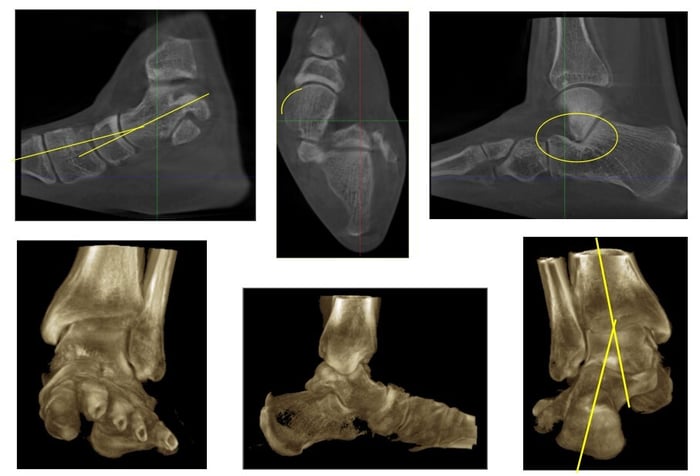

Tuttavia, oggi, la TAC in carico, come accennato sopra, è un esame fondamentale per diagnosticare un piede piatto che evolve e peggiora.

Si tratta di uno studio TAC eseguito con una tecnologia che permette di acquisire l’esame in piedi.

Permette, infatti, di andare ad osservare parametri aggiuntivi:

- Faccetta sottoastragalica anteriore: l’articolazione sottoastragalica (articolazione tra calcagno e astragalo) è infatti costituita da due componenti articolari (in alcune sue varianti anatomiche addirittura da 3). Lo studio specifico della sottoastragalica anteriore in carico è un potente indice di predittività dell’evoluzione del piede piatto patologico. Ci dice se dobbiamo agire e con quanta fretta.

- Impingement sinus tarsi: indica se l’articolazione sottoastragalica è diventata pienamente artrosica e quindi deve essere riallineata con il suo sacrificio (artrodesi sottoastragalica) o se il piede piatto può essere ricostruito preservando ogni sua funzione e movimento. E’ il motivo per cui in alcuni casi è importante scegliere il momento giusto in cui operarsi: non arrivare troppo presto, ma neanche troppo tardi.

- Rielaborazione con sistema supportati da AI (Intelligenza Artificiale) per planning chirurgico e valutazione funzionale. Le immagini TAC in carico possono essere supportate da sistemi che utilizzano AI per ottenere delle valutazioni funzionali dei sovraccarichi articolari e per ottenere dei planning chirurgici che assomiglino a dei veri e propri rendering dell’intervento. Mettono in condizioni il chirurgo di sapere prima quale chirurgia eseguire, con quali strumenti e quale inclinazione o correzione sia necessaria.

La TAC in Carico ha quindi rivoluzionato la comprensione del piede piatto, ma ha anche un impatto profondo sull’operatività di chi ha a disposizione questo strumento, che, oggi è anche un vero e proprio strumento operativo.

Infatti, grazie ad applicazioni come BoneLogic (Disior – Paragon28 – Zimmer Biomet), al mio gruppo è possibile eseguire un planning delle correzioni, comprendendo ed analizzando su un modello tridimensionale l’impatto di ogni correzione scheletrica.